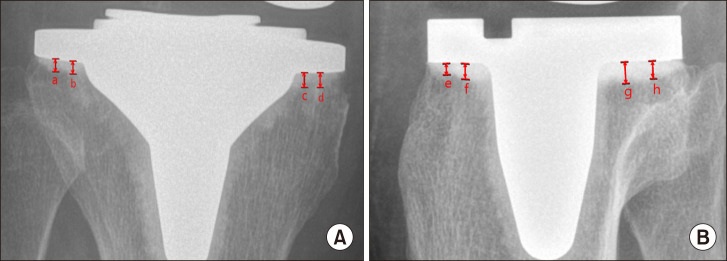

This retrospective study compared cement penetration, the radiolucent line (RLL) incidence, and clinical outcomes in total knee arthroplasty (TKA) using high-viscosity cement (HVC) versus low-viscosity cement (LVC) with a minimum follow-up of two years. We hypothesized that LVC would result in superior cement penetration and a reduced RLL incidence compared with HVC without differences in clinical outcomes. A total of 100 patients (50 HVC, 50 LVC) who underwent TKA with the same implant design were included. Cement penetration was assessed in four tibial and two femoral zones. Clinical outcomes including the VAS, WOMAC, KSS, KOOS and FJS were evaluated preoperatively and at the final follow-up visit. Postoperative complications were recorded. LVC demonstrated significantly greater cement penetration in the posterior tibial zone (3.03 mm vs. vs 2.82 mm; p=0.005) and posterior femoral zone (1.76 mm vs. 1.39 mm; p<0.000) than HVC, and no differences were observed in other zones. The RLL incidence and rates of complications including aseptic loosening and prosthetic joint infection were comparable between groups. Both groups showed significant postoperative improvements in the WOMAC, KSS, and KOOS, with no intergroup differences preoperatively and postoperatively. LVC demonstrated superior cement penetration in select zones, which may enhance implant fixation. However, there were no differences in the RLL incidence or clinical outcomes between the HVC and LVC groups. Both cements provided satisfactory fixation and clinical results, suggesting that either may be appropriate based on surgical preferences and fixation goals.

这项回顾性研究比较了使用高粘度水泥(HVC)和低粘度水泥(LVC)的全膝关节置换术(TKA)的骨水泥穿透、放射性透光线(RLL)发生率和临床结果,随访时间至少为两年。我们假设,与HVC相比,LVC会导致更好的水泥穿透性和RLL发生率降低,但临床结果没有差异。共纳入100例采用相同种植体设计的TKA患者(50例HVC, 50例LVC)。在四个胫骨区和两个股骨区评估水泥穿透。术前及最终随访时分别评估VAS、WOMAC、KSS、KOOS、FJS等临床指标。记录术后并发症。LVC在胫骨后区表现出更大的水泥渗入(3.03 mm vs. 2.82 mm;P =0.005)和股后区(1.76 mm vs. 1.39 mm;p